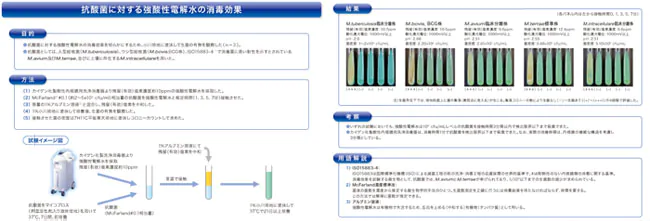

特徴6、徹底した感染予防

近年、医療機器を介した患者様への病原体の感染事例が問題となっております。当院では検査毎に内視鏡自動洗浄器での洗浄・消毒を行っております。

当院では検査に使用したすべての内視鏡を毎検査ごとに、内視鏡用洗浄消毒器(クリーントップWM-SⅡ、カイゲンファーマ社製)で消毒しております。これによって内視鏡検査を介する大腸菌O-157やピロリ菌などの細菌、肝炎ウイルスなどの病原体の感染を制御します。また強酸性電解水は人に対する安全性に優れ環境にも優しいとされていますので安心して検査をお受けください。